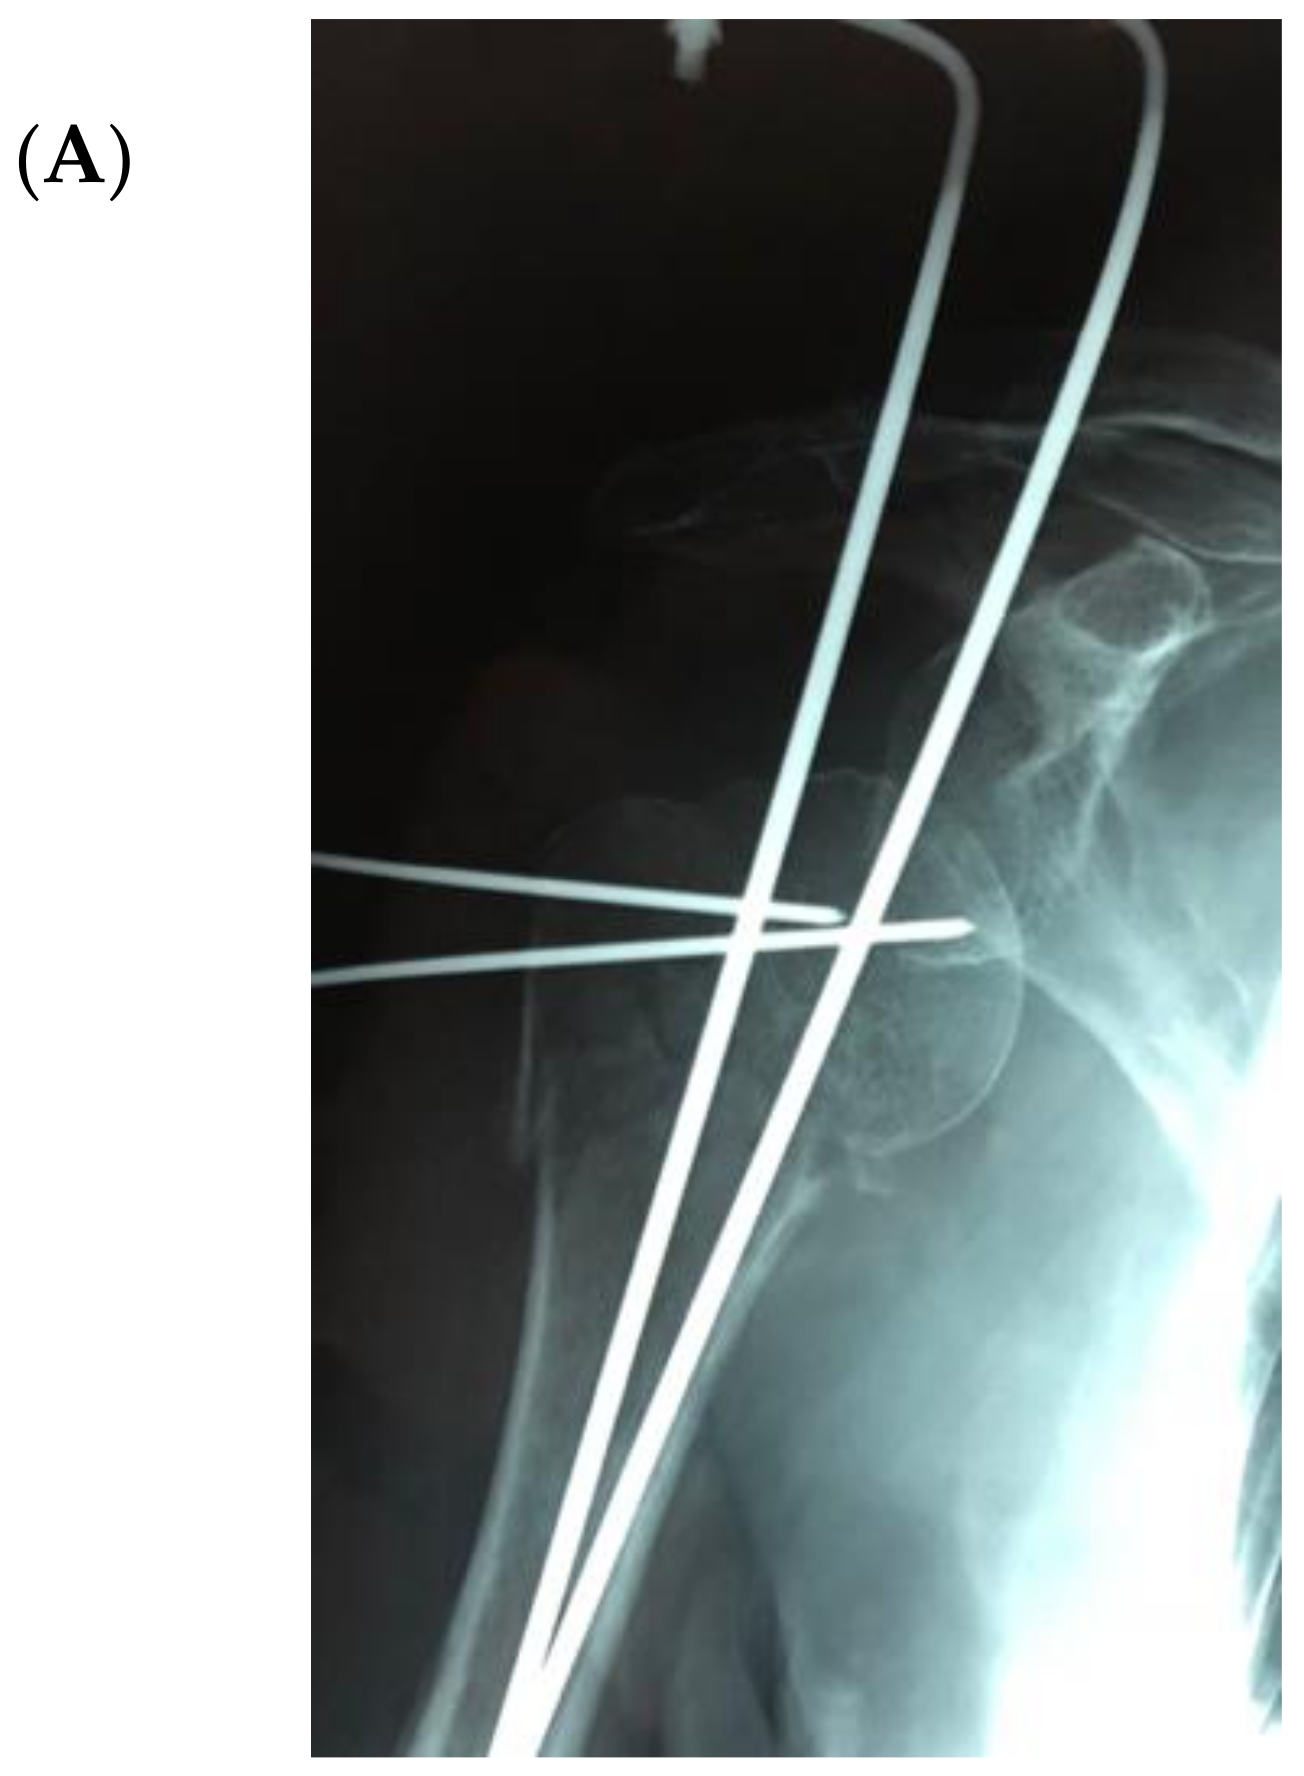

(A) The X-ray of a case of an infected proximal humerus fracture sequelae, originally treated with a plate. (B) After plate removal, the first RSA was implanted, which subsequently dislocated, resulting in infection. (C) A two-stage procedure was performed: removal of the RSA, debridement and implant of a cement antibiotic spacer with vancomycin. (D) Spacer X-ray postoperative image.

Figure 4 illustrates an infected case of proximal humerus fracture sequelae, originally treated with a plate, then treated according to our protocol. After plate removal, an RSA was implanted, which subsequently dislocated, resulting in infection. A two-stage procedure was performed: removal of the RSA, debridement, and implantation of a cement antibiotic spacer with vancomycin. MicroDTTect identified the pathogen (Cutibacterium acnes), intravenous antibiotics and infection eradication followed.